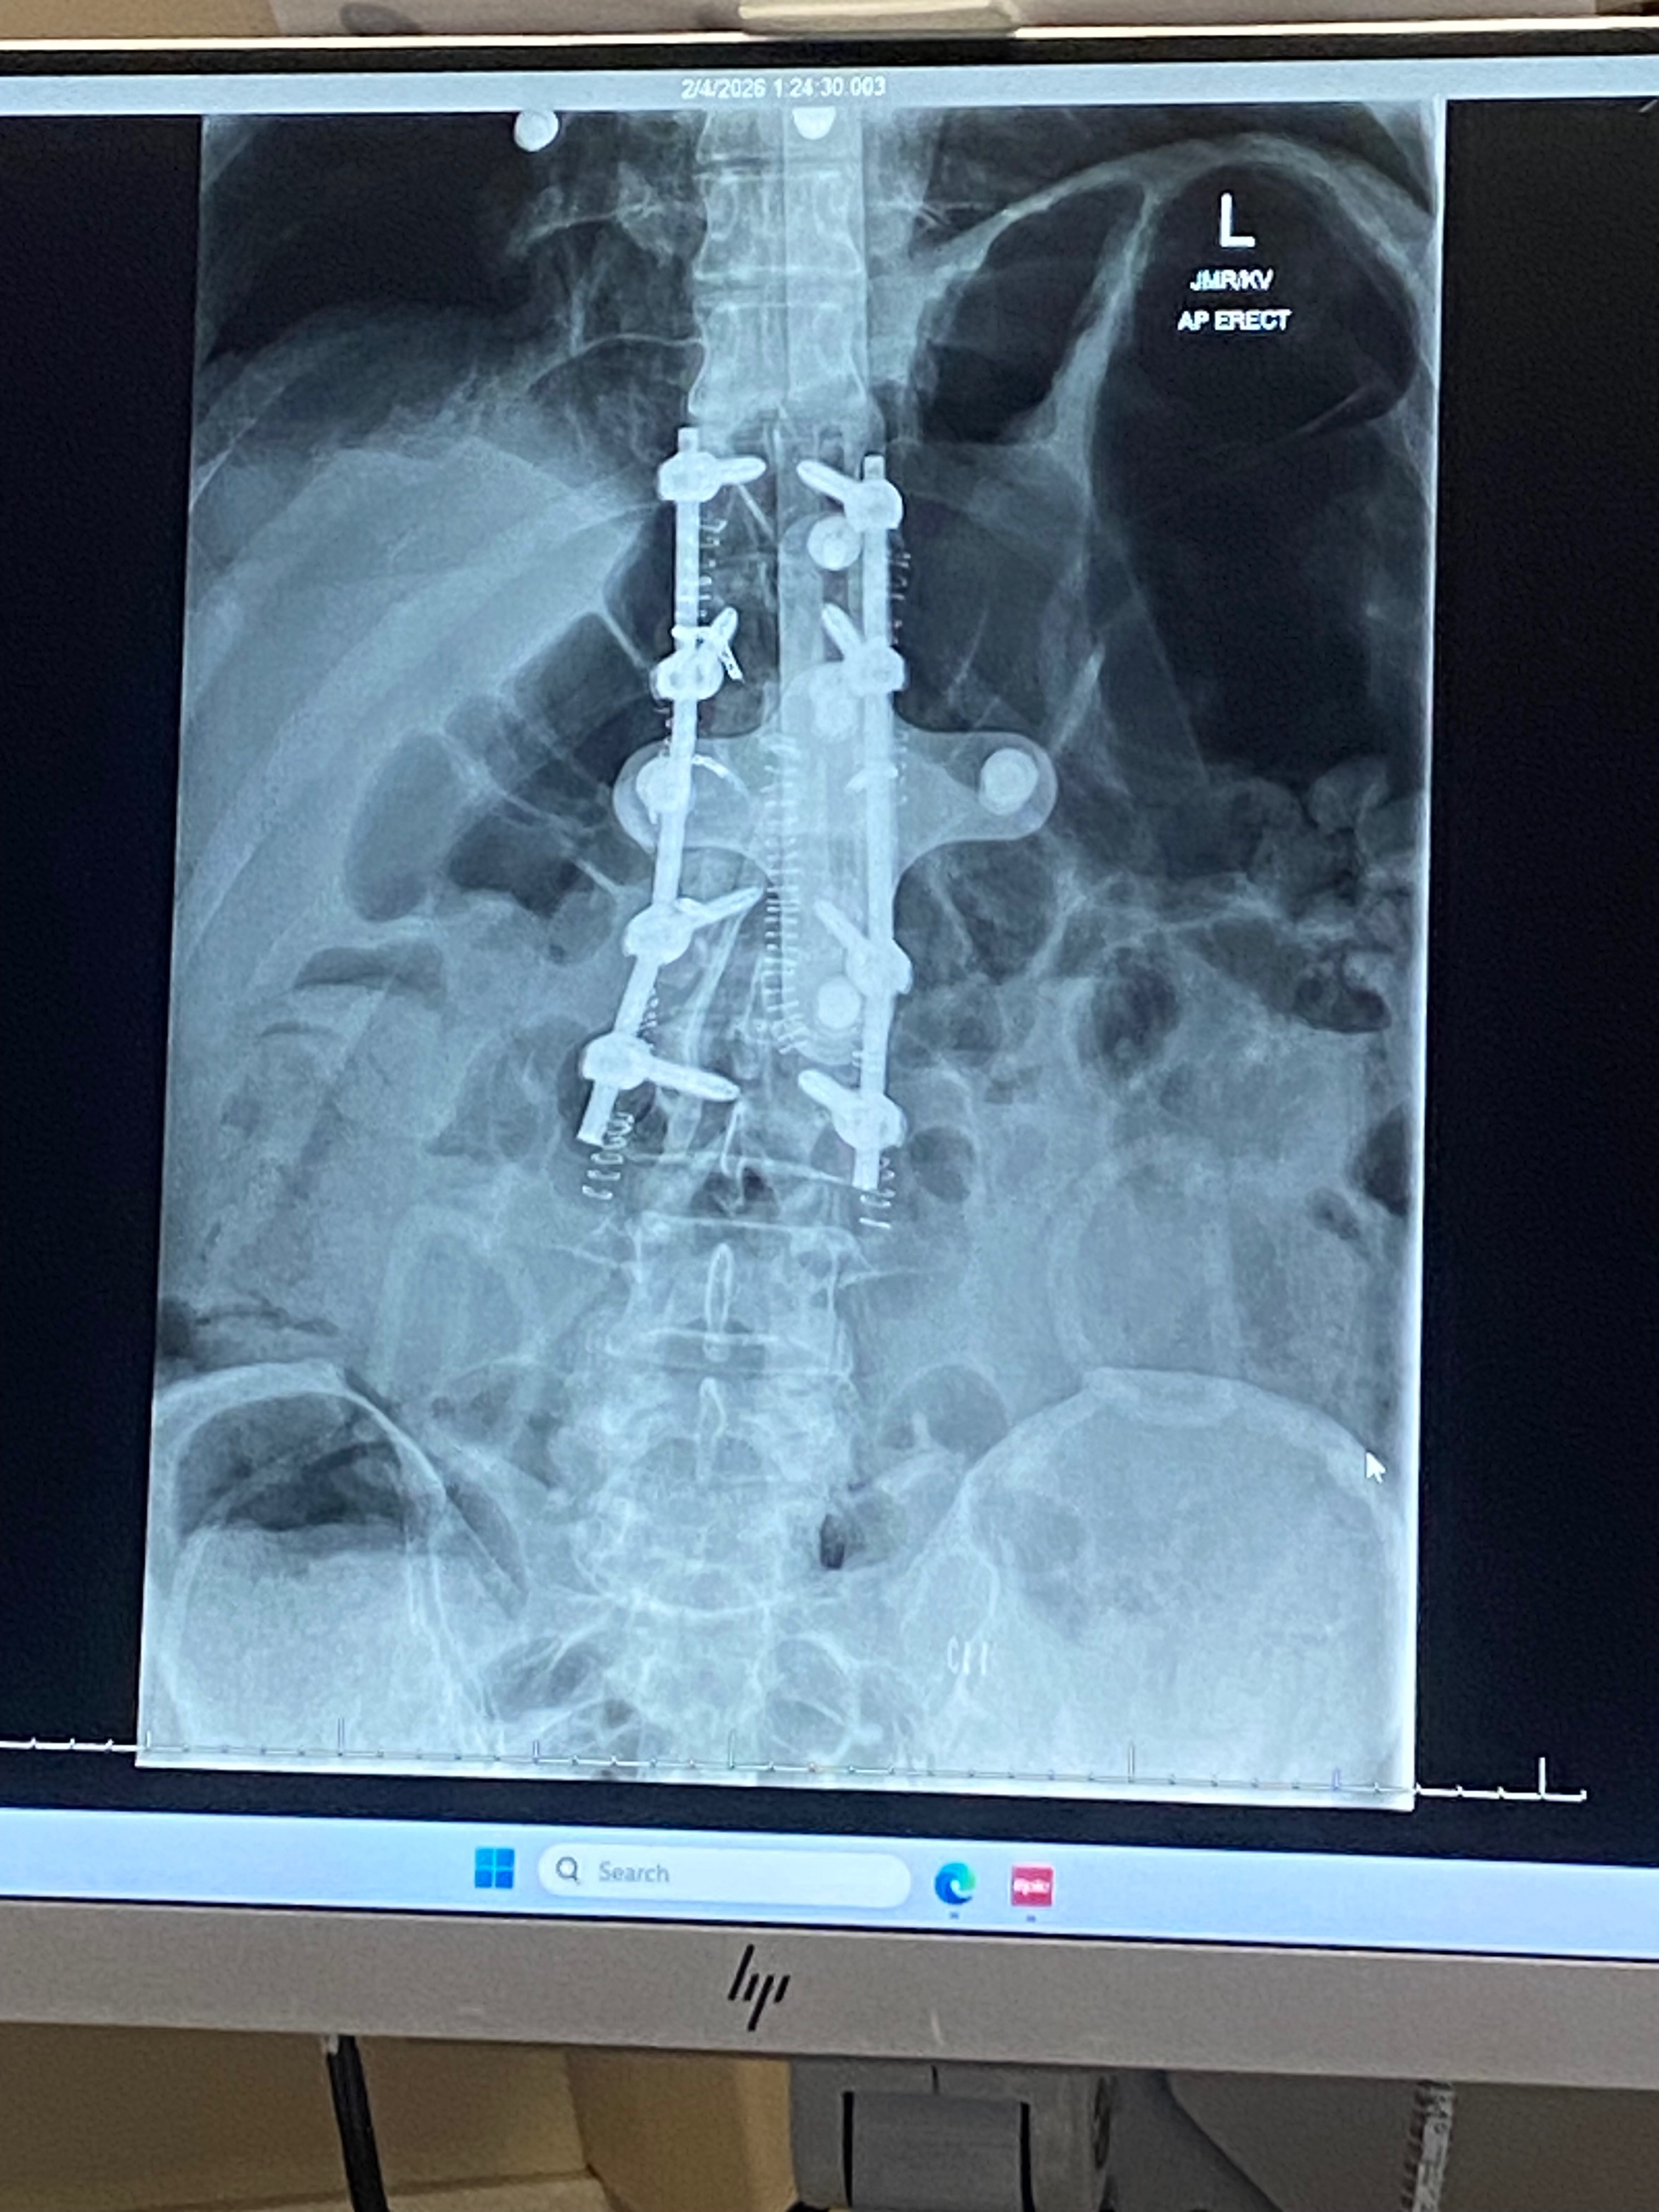

Ken has since undergone spinal surgery. His recovery is going okay, but it has been very difficult. Doctors were able to remove a tumor the size of a fist, but some of the tumor remains because removing it completely was too risky. He also lost a significant amount of blood during surgery and required a blood transfusion. Ken is still in a lot of pain because the remaining tumor is pressing on his nerve, but his surgeon, neurologist, doctors, nurses, and the entire medical team — who have been truly amazing — believe that radiation treatment can destroy the remaining tumor.